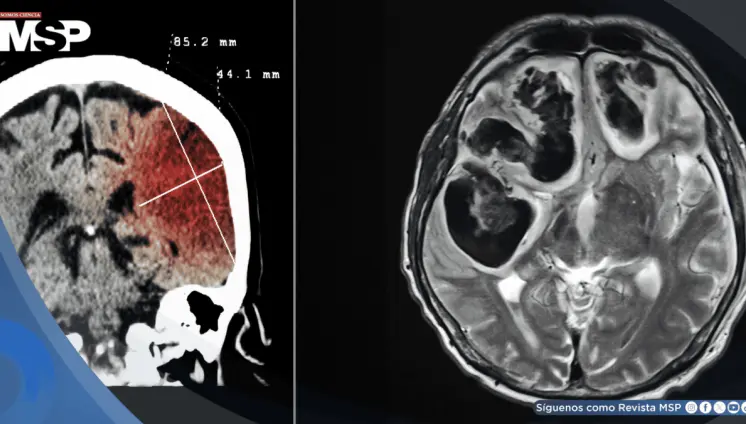

Aunque muchos tumores cerebrales comparten síntomas similares, su diagnóstico y tratamiento dependen de factores como la localización, el comportamiento biológico y la afectación funcional que producen en el paciente.